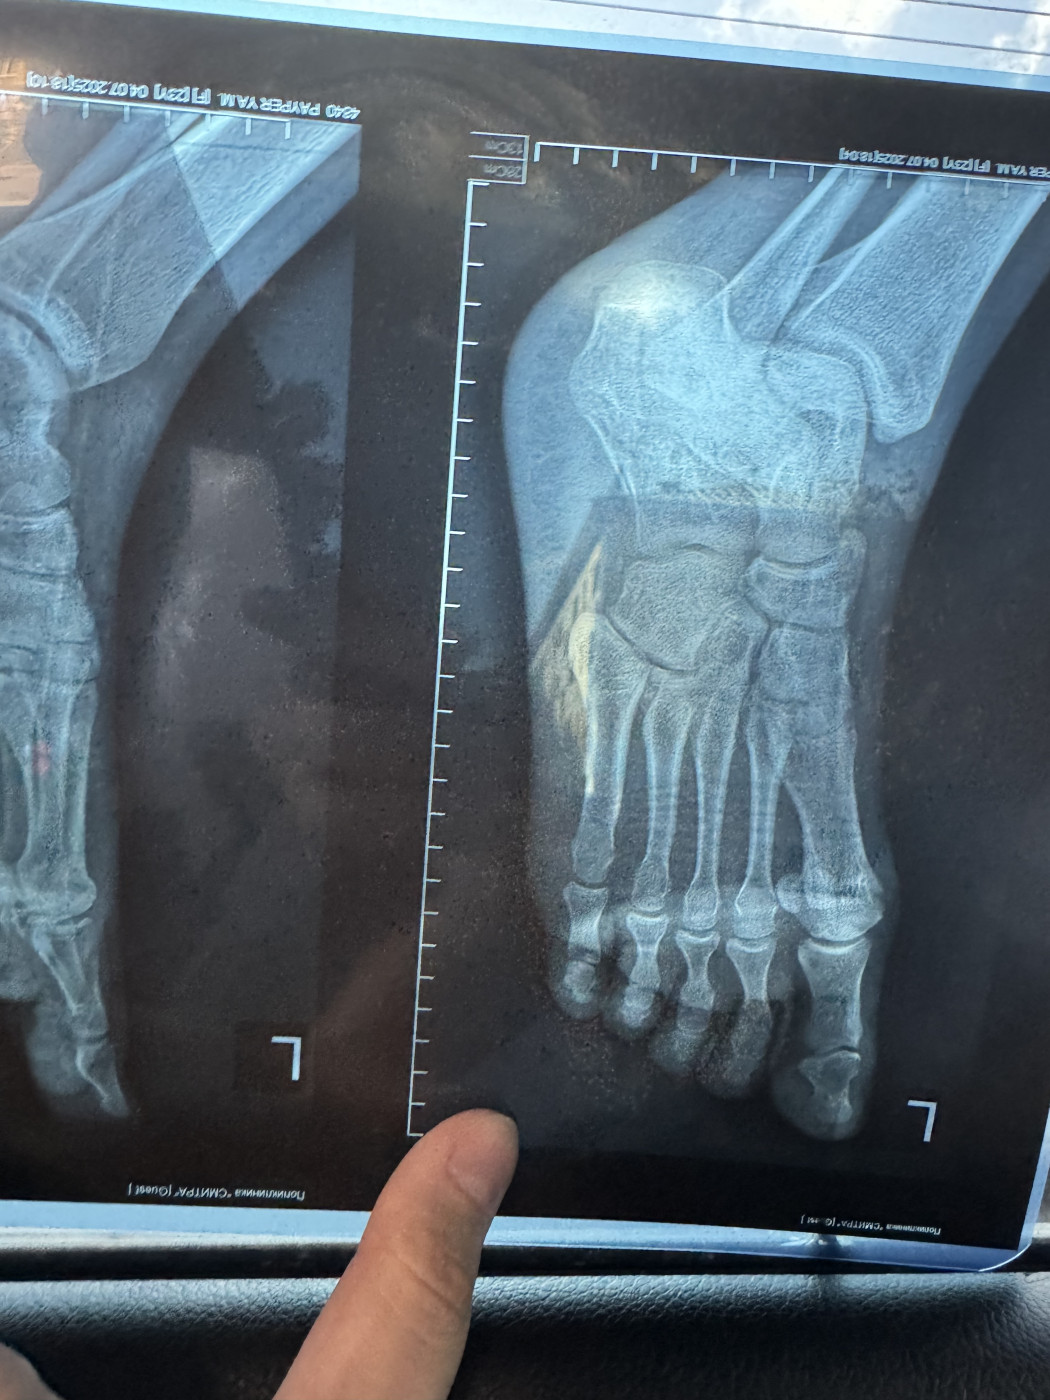

Перелом пяточной кости   2 ответа

Здравствуйте, через 30 дней после перелома сделали рентген снимок, который оказался намного детальней первого, я на нем увидел странность, а врач не дает четкого ответа, прикладываю снимок, посмотрите пожалуйста, нет ли второго перелома в правой части кости, сейчас врач сказал ходить в лангете еще 14 дней, после этого снять САМОМУ, без приема, и начать реабилитацию, пытаться наступить на ногу к 60 дню от перелома